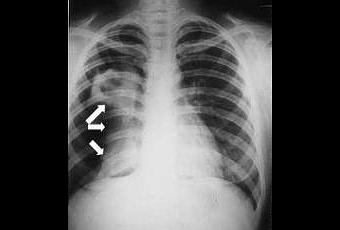

El causante de esta enfermedad infecciosa es la bacteria Mycobacterium tuberculosis, un organismo que casi siempre afecta a los pulmones. La afección es curable y se puede prevenir. La transmisión persona a persona se produce a través del aire, en la tos, estornudo o cuando alguien escupe. Curiosamente, una tercera parte de la población mundial está infectada de forma asintomática, latente. Durante dicho periodo, no se transmite la infección. El riesgo de enfermar, una vez infectada una persona, a lo largo de su vida, es del 10%.